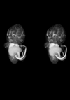

Human Embryo

Carnegie Stage 18 (44 post-ovulatory days)

Most embryos at stage 18 are approximately 44 postovulatory days old and measure 13-17 mm in length. Distinguishing criteria for this stage include cervical and lumbar flexures, distinct notching in the hand plate, the first appearance of the elbow, eyelid folds may appear in more advanced specimens, and auricular hillocks begin to form distinct parts of the external ear.

MRI Slice Selector